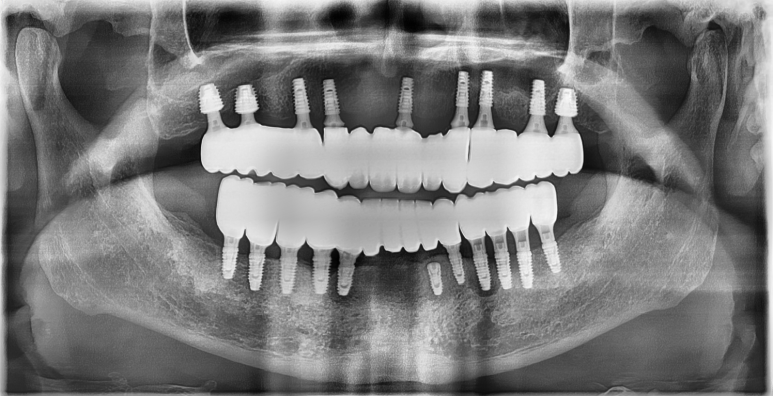

촬영일시 2024.09.01. 내원 당시 술전 파노라마 엑스레이 사진입니다. 환자분 안모 기준으로 좌측 작은 어금니 부위(#24,25번 치아 부위)를 제외한다면 뼈의 상태를 수술하기에 양호한 편에 속합니다. (저희는 이런 경우를 운동장 같은 뼈라고 비유하곤합니다 ㅎㅎ) 촬영일시 2024.11.01. 좌우측 어금니 부위에는 상악동거상술(수직접근법)을 동반하여 임플란트를 심어드렸구요. 앞니 부위는 뼈이식을 통해 뼈의 두께를 늘려드렸습니다. 처음 말씀드렸던 환자분 기준 왼쪽 작은 어금니 부위(#24,25 치아 부위)에도 뼈이식을 충분히 하여 골재생을 도모했습니다. 가이드나 스탠트의 도움이 전혀 없이 상악동 거상술 및 골이식을 포함하여 임플란트 9개를 식립하는데 대략 40분이 좀 안걸렸습니다. 임플란트간 위치와 기울기가 보기 좋게 식립되었습니다 ㅎㅎ (매일매일 하다보면 수술이란게 환자분들 걱정만큼 오래 걸리지 않습니다 ㅎㅎ) 임플란트가 좋은 위치에 식립되고 잘 완성된 모습입니다. 촬영일시 2024.12.10. 환자분께선 걱정을 많이 하셨는데 순식간에 끝났다며 좋아하셨습니다 ㅎㅎ 상악동 거상술 부위와 골이식 부위가 단단하게 굳는 기간 동안 무리하지 않도록 주의를 당부드렸습니다.

촬영일시 2024.12.10. 지금까지 365일 열린 가까운 서울대학교 치과병원을 지향하는 미추홀구치과 365서울앞선치과였습니다. 감사합니다. ※ 365서울앞선치과의원의 모든 포스팅은 각 진료과 의료진이 직접 작성합니다. 365서울앞선치과의원 블로그의 임상 케이스 게시물은 환자분께 의학적으로 정확하고 상세한 정보를 드리기 위해 각 진료과 의료진이 직접 작성하며, 모든 증례 사진은 본원 의료진이 직접 시술한 증례를 촬영한 것으로, 의료법 제23조, 제56조에 의거하며 환자분의 동의를 얻어 포스팅에 사용하였습니다. 또한 해당 케이스는 본 환자분의 치료 결과이며, 환자 상태에 따라 치료의 결과는 달라질 수 있습니다. |